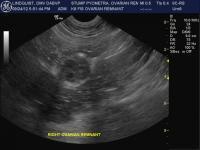

Ovarian Remnant